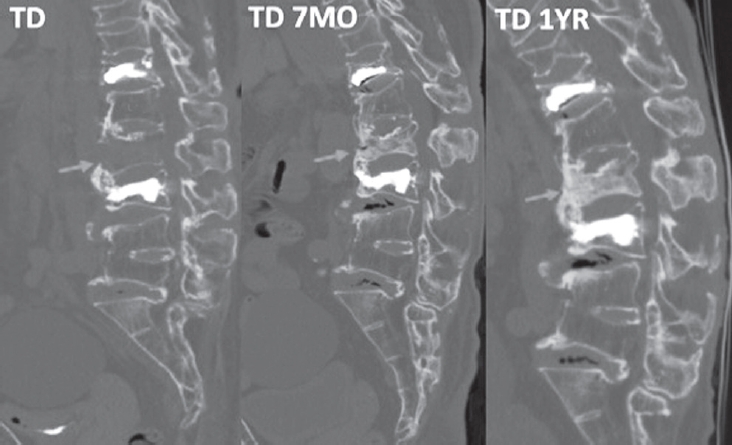

At six months, she was able to ambulate with a walker. After completing six monthly doses of romosozumab, therapy was transitioned to denosumab for long-term maintenance. One-year follow-up CT demonstrated complete consolidation of the L2 fracture with substantial intravertebral bone fill-in (Fig. 3).

Fig. 3.

Follow-up computed tomography demonstrating interval consolidation of L2 vertebral fracture.

Fig. 3. Follow-up computed tomography demonstrating interval consolidation of L2 vertebral fracture.